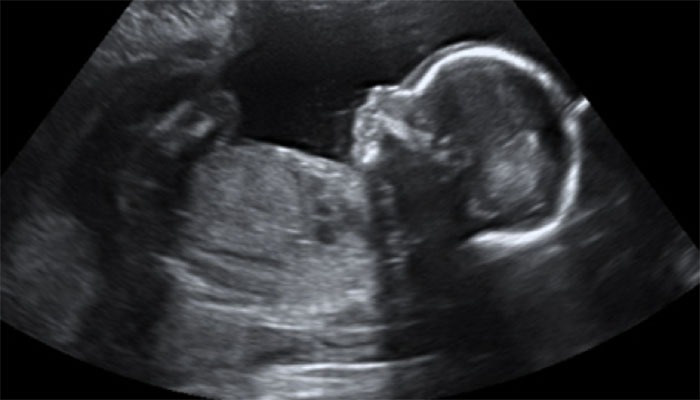

An Obstetrical (OB) ultrasound exam is an exciting part of pregnancy and a chance to see your baby before it is born. The test may be performed at various times during your pregnancy to study the pregnancy process and to evaluate your health and your baby’s health and growth while he or she is still in your uterus.